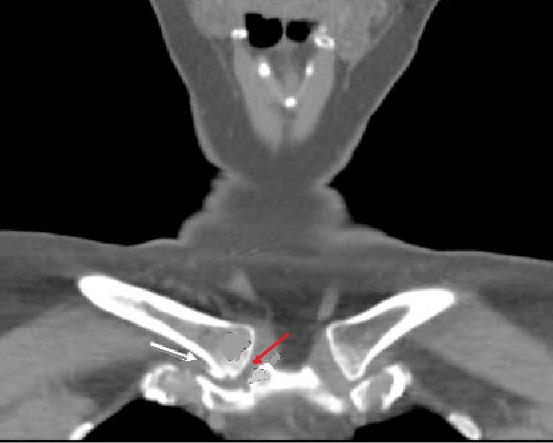

Même cas en coupe TDM coronal

( frontal ) avec image de

oedème de la moelle

osseuse dans sous-chondral gauche et élargissement et

épaississement du cartilage de articulation manubrium -costale

gauche etr en vue très nette |